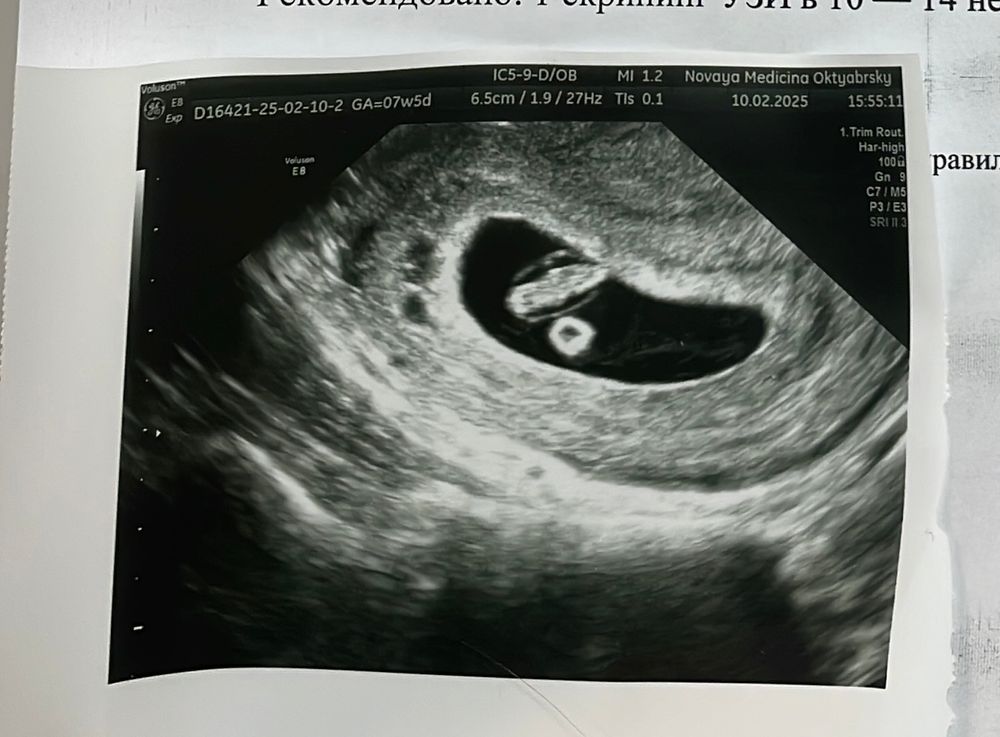

Ольга в Благополучная беременность 10 месяцев Что за темные пятна на снимке узи ? Анализы, скрининги Беременность 7 недель, рядом с плодным яйцом увидела несколько тесных пятен, что это такое? Посмотрите еще 20 записей на эту тему Отменить Ответить Повышается д димер Ещё по 1 скринингу высокий риск ПЭ 1:19 Чаты Беременных Выберите чат: Январята-2026 Февралята-2026 Мартята-2026 Апрелята-2026 Майчата-2026 Июнята-2026 Июлята-2026 Августята-2026